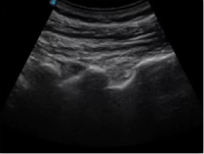

不同的探頭對(duì)應(yīng)于不同的臨床領(lǐng)域,不同的探頭頻率也應(yīng)用于不同的人體組織。超聲波在人體中的衰減與探頭頻率有關(guān),探頭頻率越高,穿透力越弱,分辨率越高,而探頭頻率越低,穿透力越強(qiáng),分辨率越低。因此在檢查淺表器官時(shí)應(yīng)選用高頻探頭,而檢查深部臟器時(shí)則選用穿透性強(qiáng)的低頻探頭。